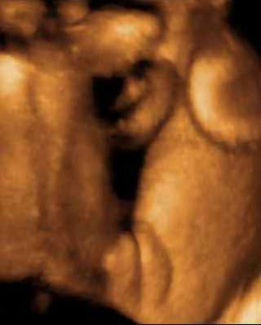

Manos Pies Niņa Niņo Otro Niņo

Niņa